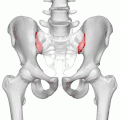

Крестцово-подвздошные суставы (левый и правый) показаны красным

- Крестцово-подвздошный сустав (лат. articulatio sacroiliaca) — образован ушковидными поверхностями тазовой кости и крестца. Включает связки: 1) вентральные крестцово-подвздошные (ligg.sacroilica ventralia), 2) дорсальные крестцово-подвздошные (ligg.sacroilica dorsalia) 3) межкостные крестцово-подвздошные (ligg.sacroilica interossea) 4) подвздошно-поясничные (ligg.iliolumbale).